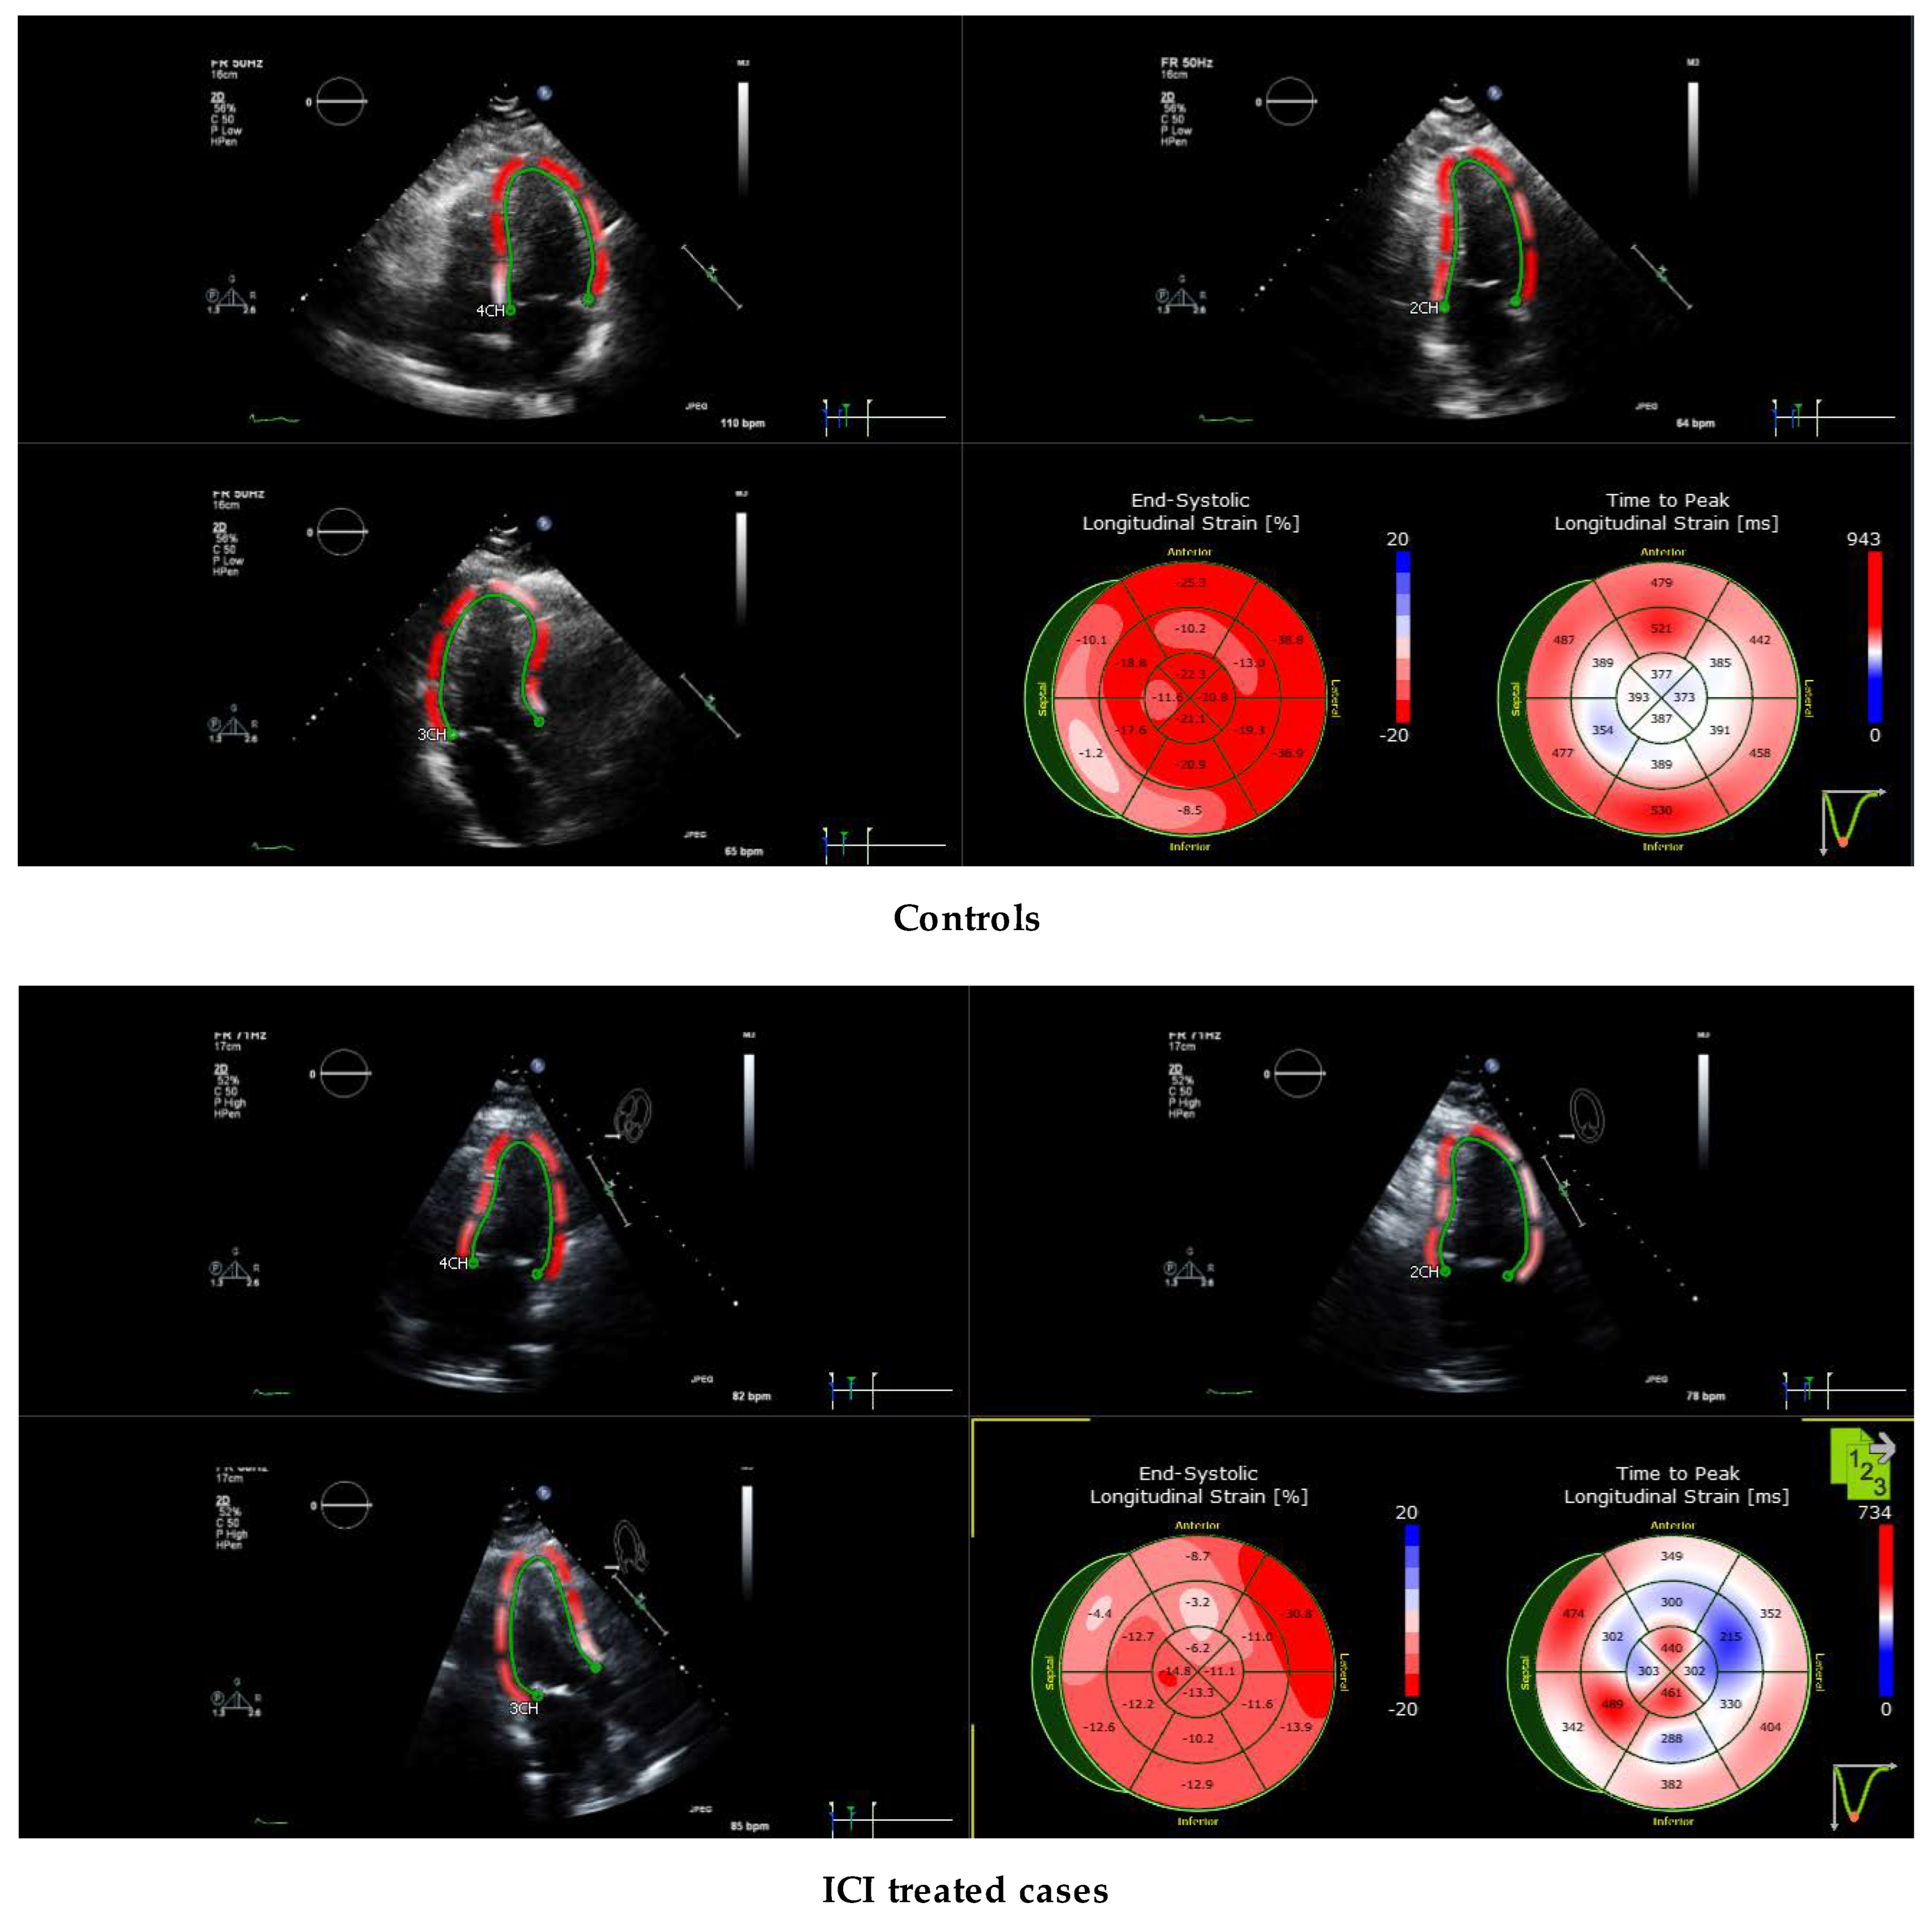

2.4. Echocardiography Protocol for Strain Evaluation

3.6. Echocardiographic Characteristics

3.8. Comparison of Echocardiography vs. Cardiac Magnetic Resonance Imaging-Based Strains